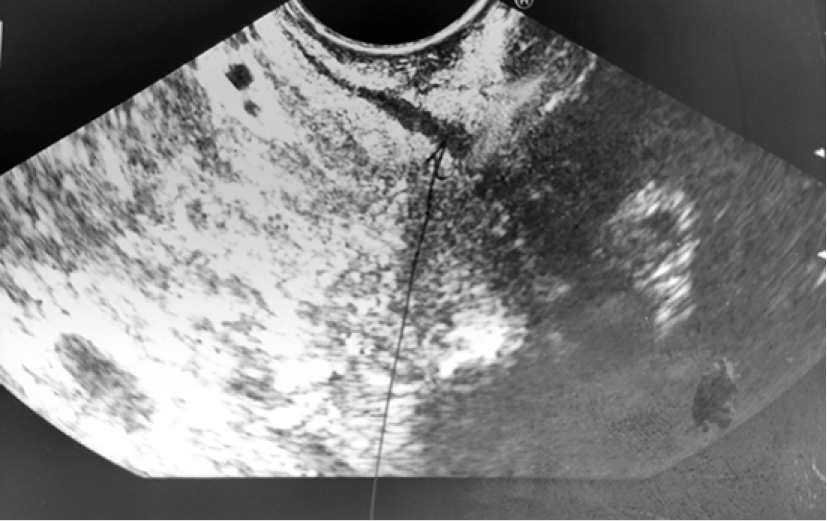

С диагнозом: «Tumor брюшной полости» поступил 02.07.2019 г. в хирургическое отделение КГБУЗ «Городская больница № 5 г. Барнаула», где провели уточняющую диагностику – эндоультрасонография от 03.07.2019 г. Видеогастроскоп проведён в желудок. Стенки желудка хорошо расправляются воздухом. В просвете желудка на большой кривизне дистальной части тела желудка на 2/3 шаровидное эластичное выбухание с подвижной гиперемированной слизистой оболочкой диаметром до 70 мм (рис. 5–7), эндосонограф свободно проведён. Сканирование в режиме 7,5–10,0 МГц. Полостное жидкостное образование диаметром 63 мм, пристеночно содержит гипоэхогенную ткань толщиной местами до 15 мм. Капсула гиперэхогенная до 1,4 мм. ЦДК (-). Образование расположено в подслизистом слое. Чётко прослеживается мышечный слой за её пределами (рис. 8, 9). Между желудком и печенью гипоэхогенная ткань с наличием сосудов и анэхогенной полостью до 10 мм (рис. 10).

Рис. 8. Образование расположено в подслизистом слое. Чётко прослеживается мышечный слой за её пределами

Рис. 9. Образование расположено в подслизистом слое. Чётко прослеживается мышечный слой за её пределами